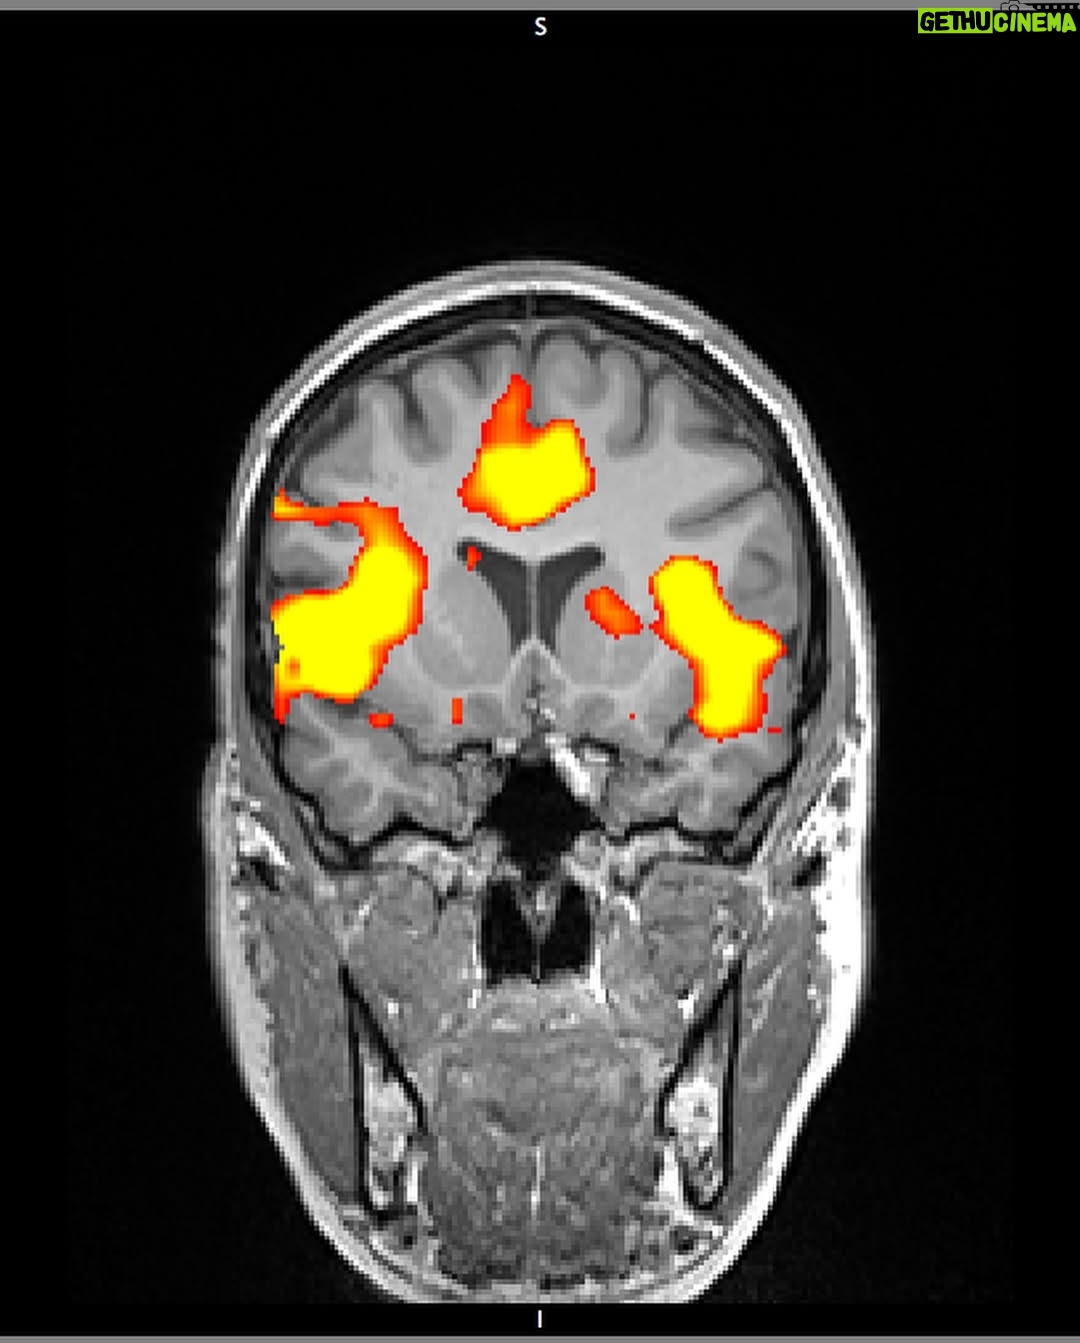

37.9K Likes – Sarah McDaniel Instagram

Caption : INNER LANDSCAPES full stylistic pilot in bio Director: @krotchy Cinematographer: @ty_mcgrath 1AC: @alex_dametto 2AC: @moshwarrior Gaffer: @liamvanderploeg Music: @bdbender VFX: @lucashrubizna Rotoscoping: @getcrspy Color: @sgllng Headpiece @lance.v.moore Special Thanks @northofnowfilms & @wfw_intl – We made this piece as part of a series that explores the inner landscapes of different artists and thought leaders. More to come 🤸🏻♀️Likes : 37922

37.9K Likes – Sarah McDaniel Instagram

Caption : INNER LANDSCAPES full stylistic pilot in bio Director: @krotchy Cinematographer: @ty_mcgrath 1AC: @alex_dametto 2AC: @moshwarrior Gaffer: @liamvanderploeg Music: @bdbender VFX: @lucashrubizna Rotoscoping: @getcrspy Color: @sgllng Headpiece @lance.v.moore Special Thanks @northofnowfilms & @wfw_intl – We made this piece as part of a series that explores the inner landscapes of different artists and thought leaders. More to come 🤸🏻♀️Likes : 37922

37.9K Likes – Sarah McDaniel Instagram

Caption : INNER LANDSCAPES full stylistic pilot in bio Director: @krotchy Cinematographer: @ty_mcgrath 1AC: @alex_dametto 2AC: @moshwarrior Gaffer: @liamvanderploeg Music: @bdbender VFX: @lucashrubizna Rotoscoping: @getcrspy Color: @sgllng Headpiece @lance.v.moore Special Thanks @northofnowfilms & @wfw_intl – We made this piece as part of a series that explores the inner landscapes of different artists and thought leaders. More to come 🤸🏻♀️Likes : 37922

37.9K Likes – Sarah McDaniel Instagram

Caption : INNER LANDSCAPES full stylistic pilot in bio Director: @krotchy Cinematographer: @ty_mcgrath 1AC: @alex_dametto 2AC: @moshwarrior Gaffer: @liamvanderploeg Music: @bdbender VFX: @lucashrubizna Rotoscoping: @getcrspy Color: @sgllng Headpiece @lance.v.moore Special Thanks @northofnowfilms & @wfw_intl – We made this piece as part of a series that explores the inner landscapes of different artists and thought leaders. More to come 🤸🏻♀️Likes : 37922

37.9K Likes – Sarah McDaniel Instagram

Caption : INNER LANDSCAPES full stylistic pilot in bio Director: @krotchy Cinematographer: @ty_mcgrath 1AC: @alex_dametto 2AC: @moshwarrior Gaffer: @liamvanderploeg Music: @bdbender VFX: @lucashrubizna Rotoscoping: @getcrspy Color: @sgllng Headpiece @lance.v.moore Special Thanks @northofnowfilms & @wfw_intl – We made this piece as part of a series that explores the inner landscapes of different artists and thought leaders. More to come 🤸🏻♀️Likes : 37922

37.9K Likes – Sarah McDaniel Instagram

Caption : INNER LANDSCAPES full stylistic pilot in bio Director: @krotchy Cinematographer: @ty_mcgrath 1AC: @alex_dametto 2AC: @moshwarrior Gaffer: @liamvanderploeg Music: @bdbender VFX: @lucashrubizna Rotoscoping: @getcrspy Color: @sgllng Headpiece @lance.v.moore Special Thanks @northofnowfilms & @wfw_intl – We made this piece as part of a series that explores the inner landscapes of different artists and thought leaders. More to come 🤸🏻♀️Likes : 37922